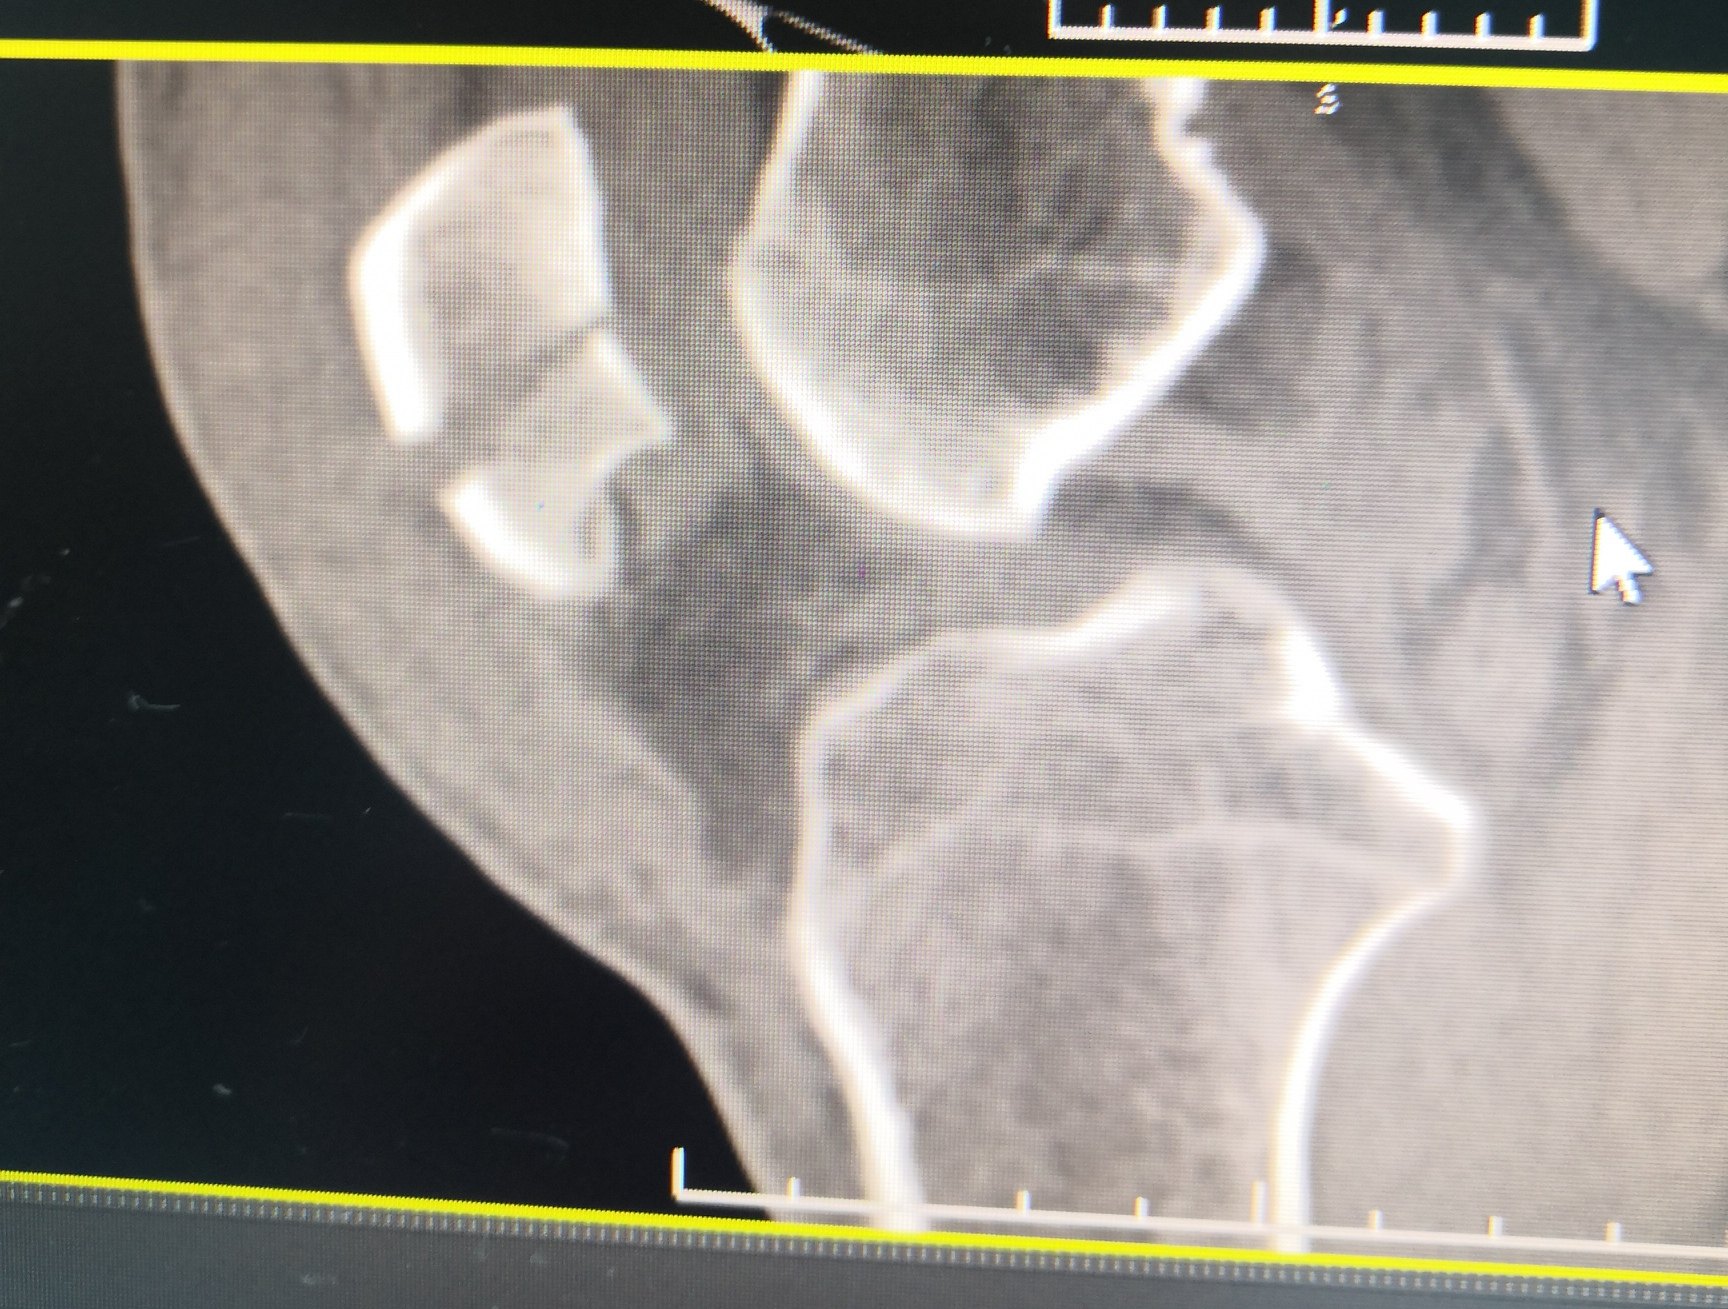

骨科学 第三节手部骨关节损伤 扫花书库

右手第5近节指远端骨折 医联

右第二掌骨骨折术后内固定存留 医联

桡骨远端骨折c3型手术 医联

骨哥手术课堂 Bennett 骨折牵引指套一牵到位

槌指骨折 突き指 指の骨折 日野市たいら手の外科 整形外科

三平面骨折 的影像诊断 影像ppt